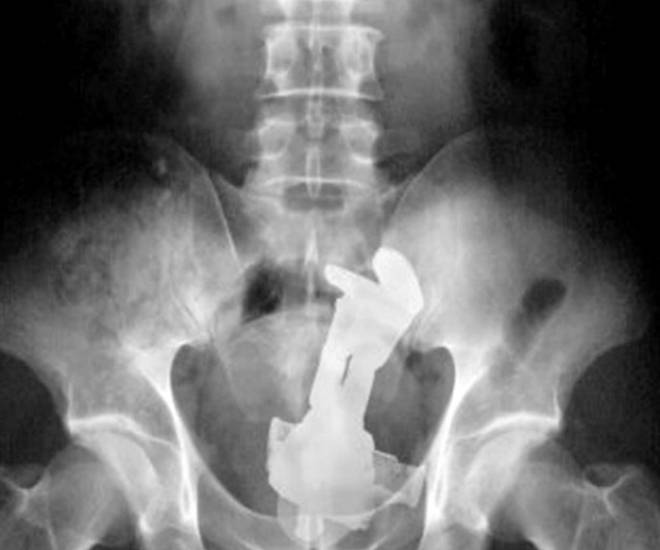

ROMA – Con il sesso i giochi erotici possono essere molto variegati. Questa “compilation” mostra però come a volte quei giochini finiscono male. Ecco infatti svariate radiografie eseguite negli ospedali di tutto il mondo.

Tutte queste persone sono state ricoverate con diversi oggetti incastrati nell’ano e non solo: dal cellulare alle chiavi di casa, passando per proiettili e giocattoli come macchinine e pupazzetti.

Anche il sex toy, a quanto pare deve essere usato responsabilmente. Specialmente quando l’oggetto è improvvisato. E chi rimane con l’oggetto incastrato cosa deve fare? Come spiegano i medici dei pronto soccorso, non bisogna provare a risolvere il problema da soli senza andare in ospedale. In molti casi infatti, alcune persone vengono ricoverate sia con l’oggetto, sia con le pinze utilizzate per recuperare l’oggetto, conficcate nell’ano.